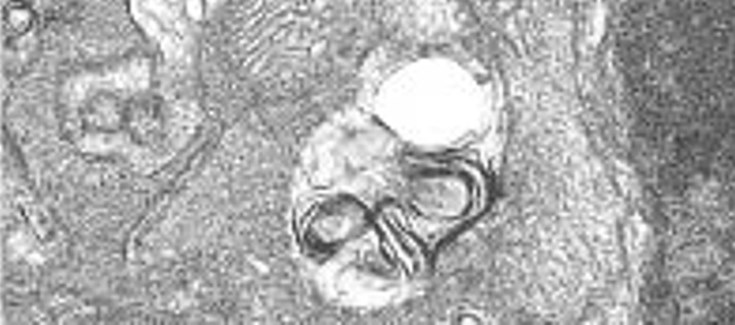

Imagen de microscopía electrónica mostrando los autofagosomas presentes en las retinas de ratones knock-out para Igf1.

Investigadoras de la U761 CIBERER, liderada por la Prof. Isabel Varela-Nieto, en colaboración con el grupo de la Dra. Ángela Martínez Valverde, perteneciente al CIBERDEM, han estudiado los efectos asociados a la neuroinflamación y la autofagia que se producen en la retina de los ratones deficientes en Igf1 durante el envejecimiento.

Los resultados de este trabajo muestran que el ratón deficiente en Igf1 presenta una inflamación crónica en la retina que se ve atenuada mediante activación de la autofagia a los 6 meses de edad, pero que no es capaz de hacerlo a los 12 meses. El estudio proporciona evidencias que apuntan a que la autofagia podría proteger frente a la inflamación crónica de la retina durante el envejecimiento en un modelo de ratón deficiente en IGF-1. El trabajo ha sido publicado recientemente en Disease Models & Mechanisms. Disease Models & Mechanisms.